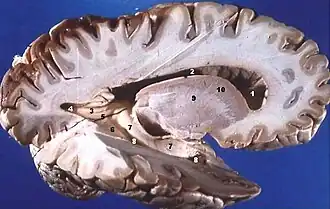

- Human brain right dissected lateral view

Grey matter is distributed at the surface of the cerebral hemispheres (cerebral cortex) and of the cerebellum (cerebellar cortex), as well as in the depths of the cerebrum (the thalamus; hypothalamus; subthalamus, basal ganglia – putamen, globus pallidus and nucleus accumbens; as well as the septal nuclei), cerebellum (deep cerebellar nuclei – the dentate nuclei, globose nucleus, emboliform nucleus, and fastigial nucleus), and brainstem (the substantia nigra, red nucleus, olivary nuclei, and cranial nerve nuclei).